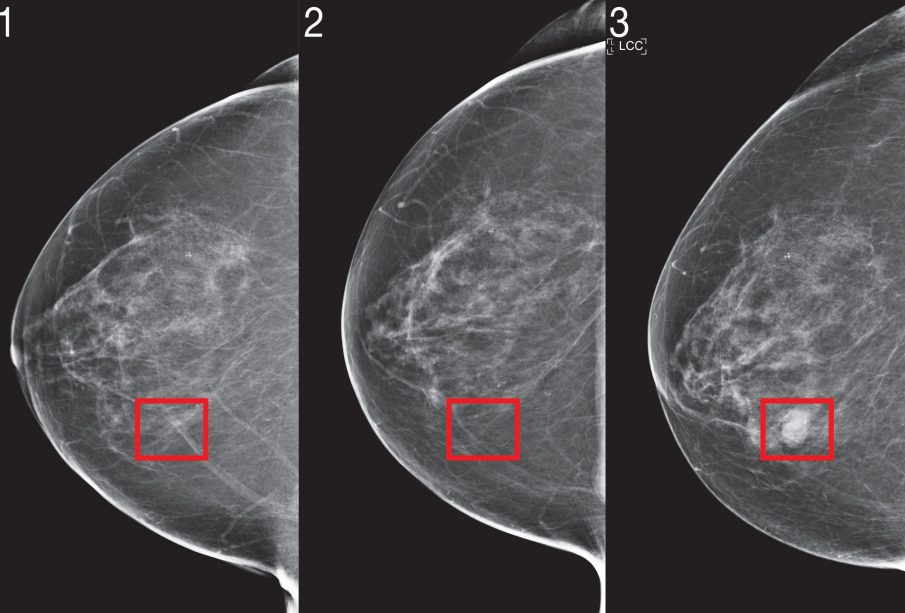

Two years ago, a team of scientists from MIT’s Computer Science and Artificial Intelligence Laboratory (CSAIL) and Jameel Clinic (J-Clinic) demonstrated a deep learning system to predict cancer risk using just a patient’s mammogram. The model showed significant promise and even improved inclusivity: It was equally accurate for both white and Black women, which is especially important given that Black women are 43 percent more likely to die from breast cancer.

Mirai was significantly more accurate than prior methods in predicting cancer risk and identifying high-risk groups across all three datasets. When comparing high-risk cohorts on the MGH test set, the team found that their model identified nearly two times more future cancer diagnoses compared the current clinical standard, the Tyrer-Cuzick model. Mirai was similarly accurate across patients of different races, age groups, and breast density categories in the MGH test set, and across different cancer subtypes in the Karolinska test set.